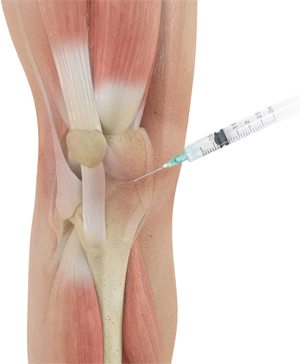

- прием медикаментов, уменьшающих болевой синдром и воспаление;

- прием нестероидных препаратов;